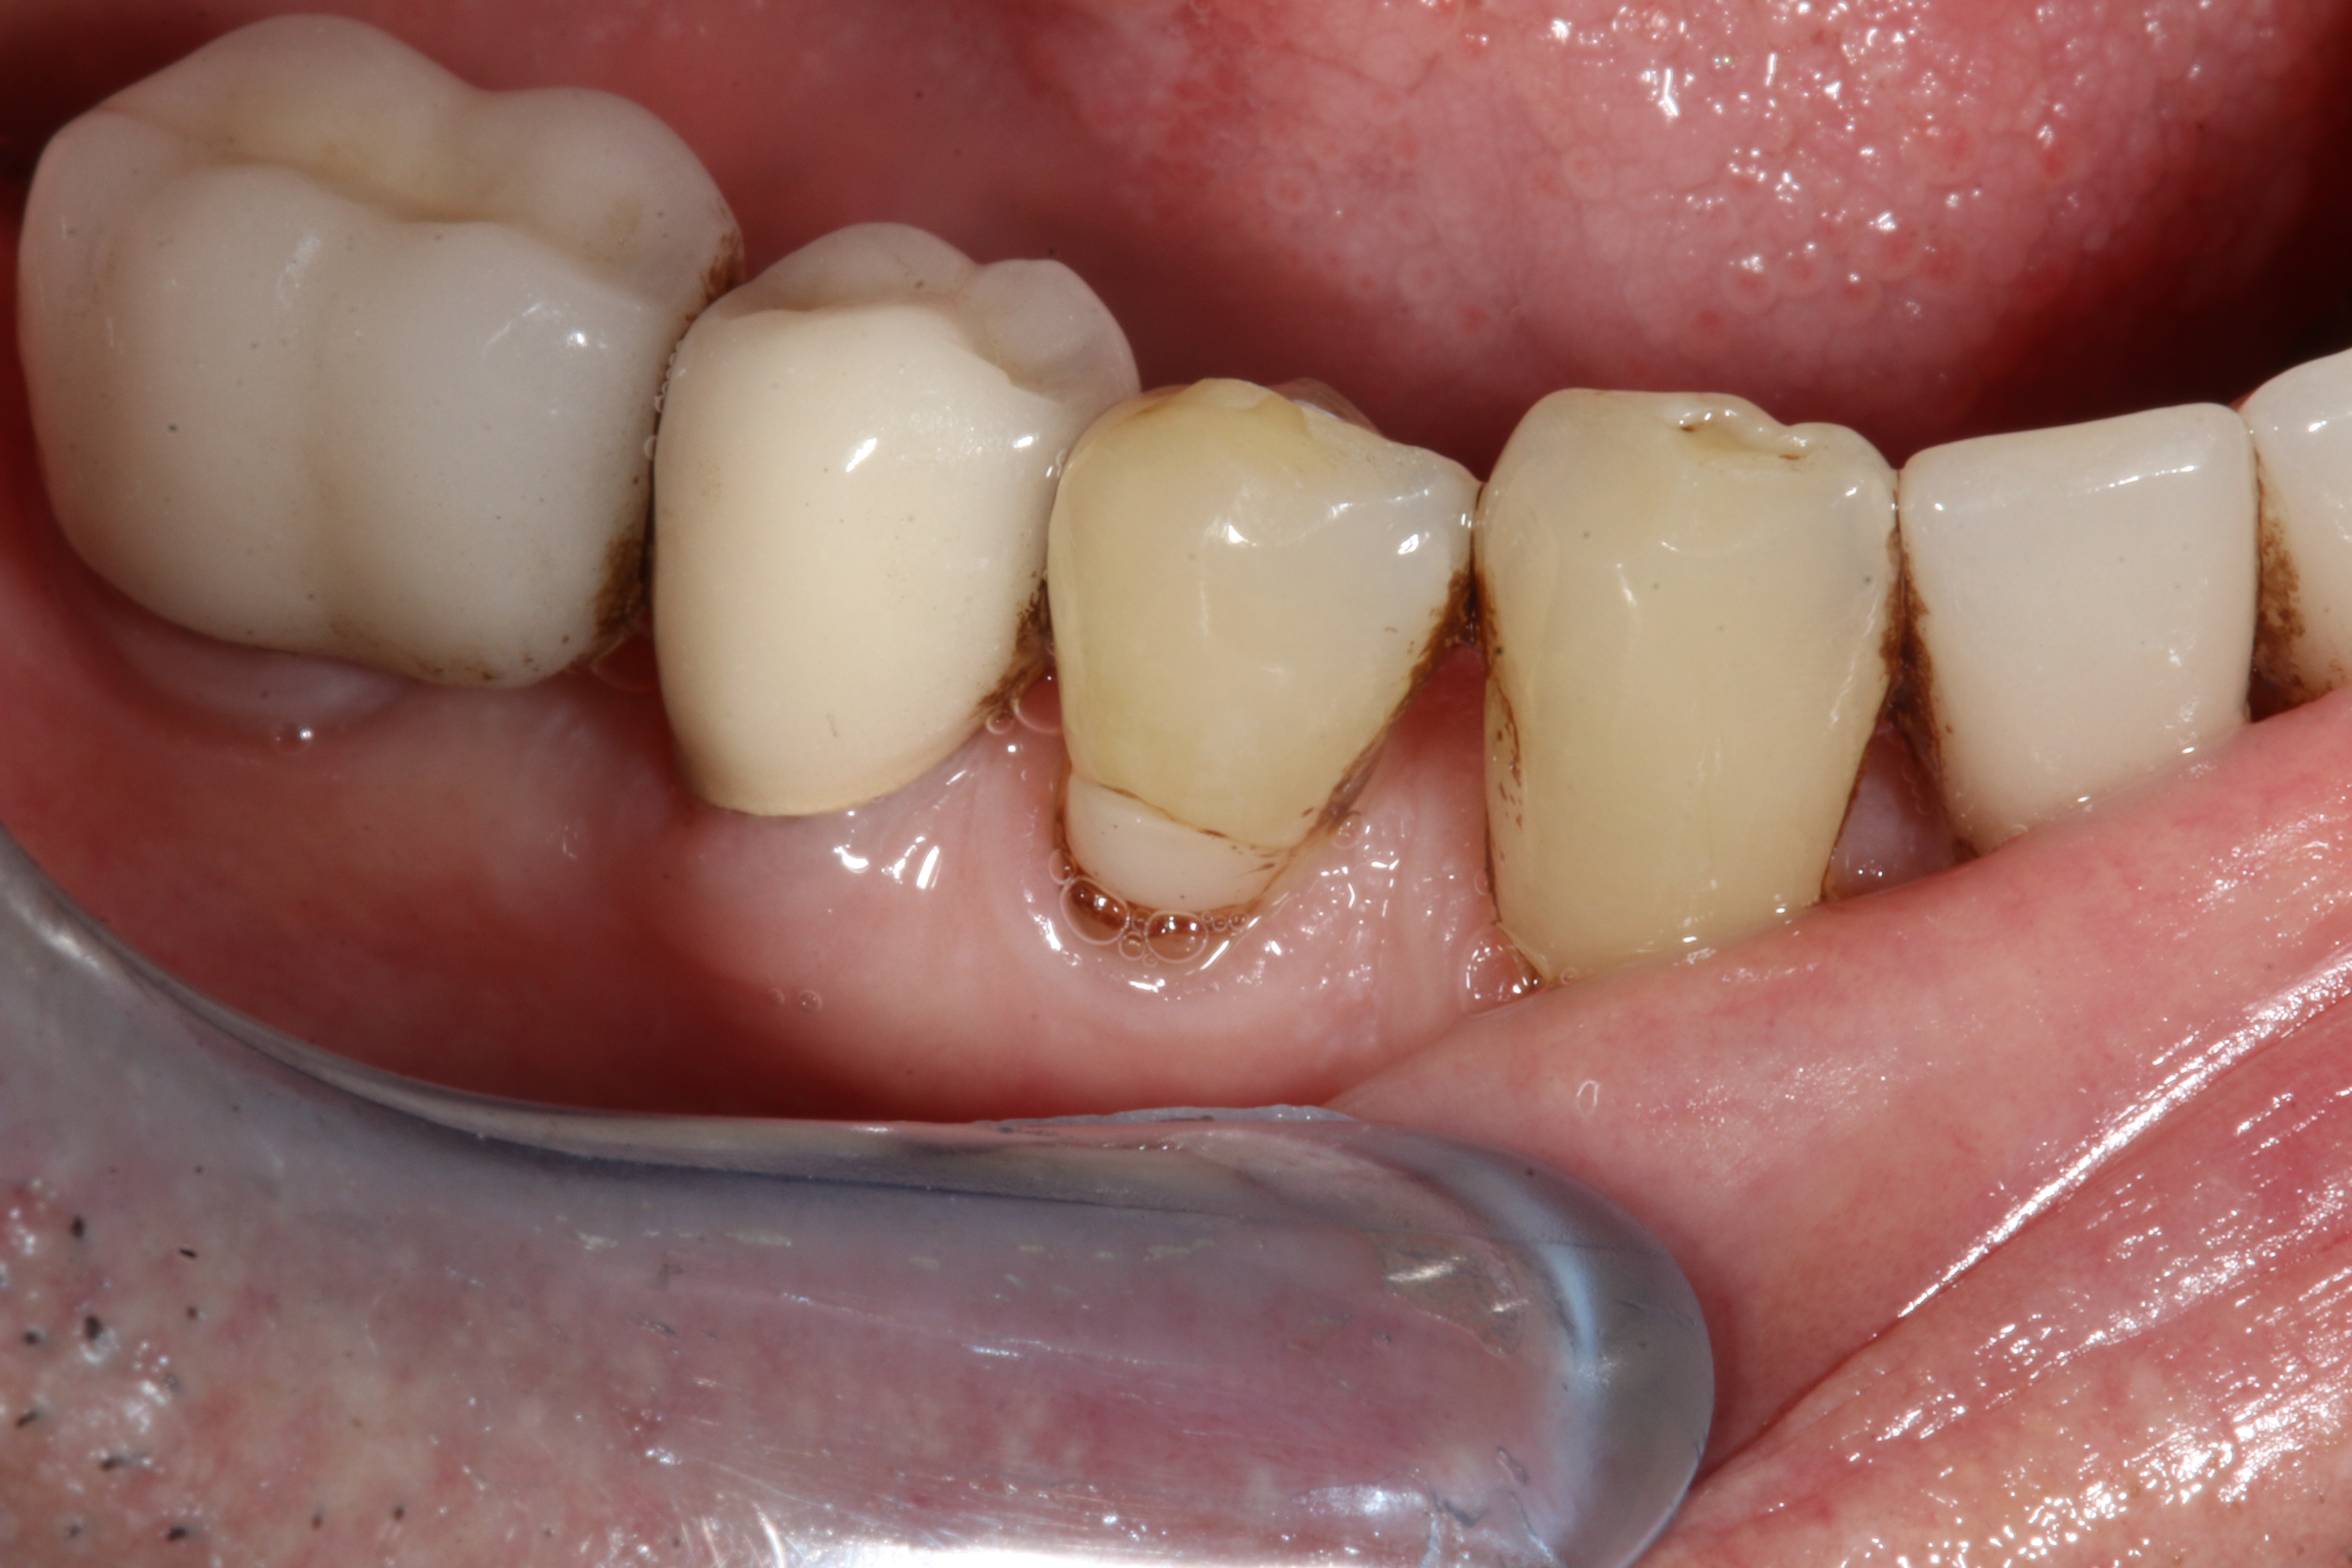

CAD/CAM dentistry is very precise. For accuracy, the preoperative, shade, bite, and upper/lower tooth scans are best taken before anesthesia and dental procedures that induce muscle fatigue (Figure 3). After infiltration anesthesia with 1 carpule of articaine hydrochloride 4% and epinephrine 1:100,000 injection, the temporary was removed. Occlusal reduction of 2.0 mm was precise and defined with an 828Y depth cutting bur to meet restorative requirements (Figure 4), and the post space was restored. Axial reduction and shoulder margination were performed with a coarse KS1 bur. After smoothing of the preparation, a 15% aluminum chloride topical gingival retraction paste was injected and compressed into the sulcus, then thoroughly rinsed with water and air-dried, before scanning of the tooth preparation and critical adjacent anatomy (Figure 5 and Figure 6).

Fig 4. Depth cutting allows precision reduction to avoid overreduction and compromise of restorative strength.

Figure 4